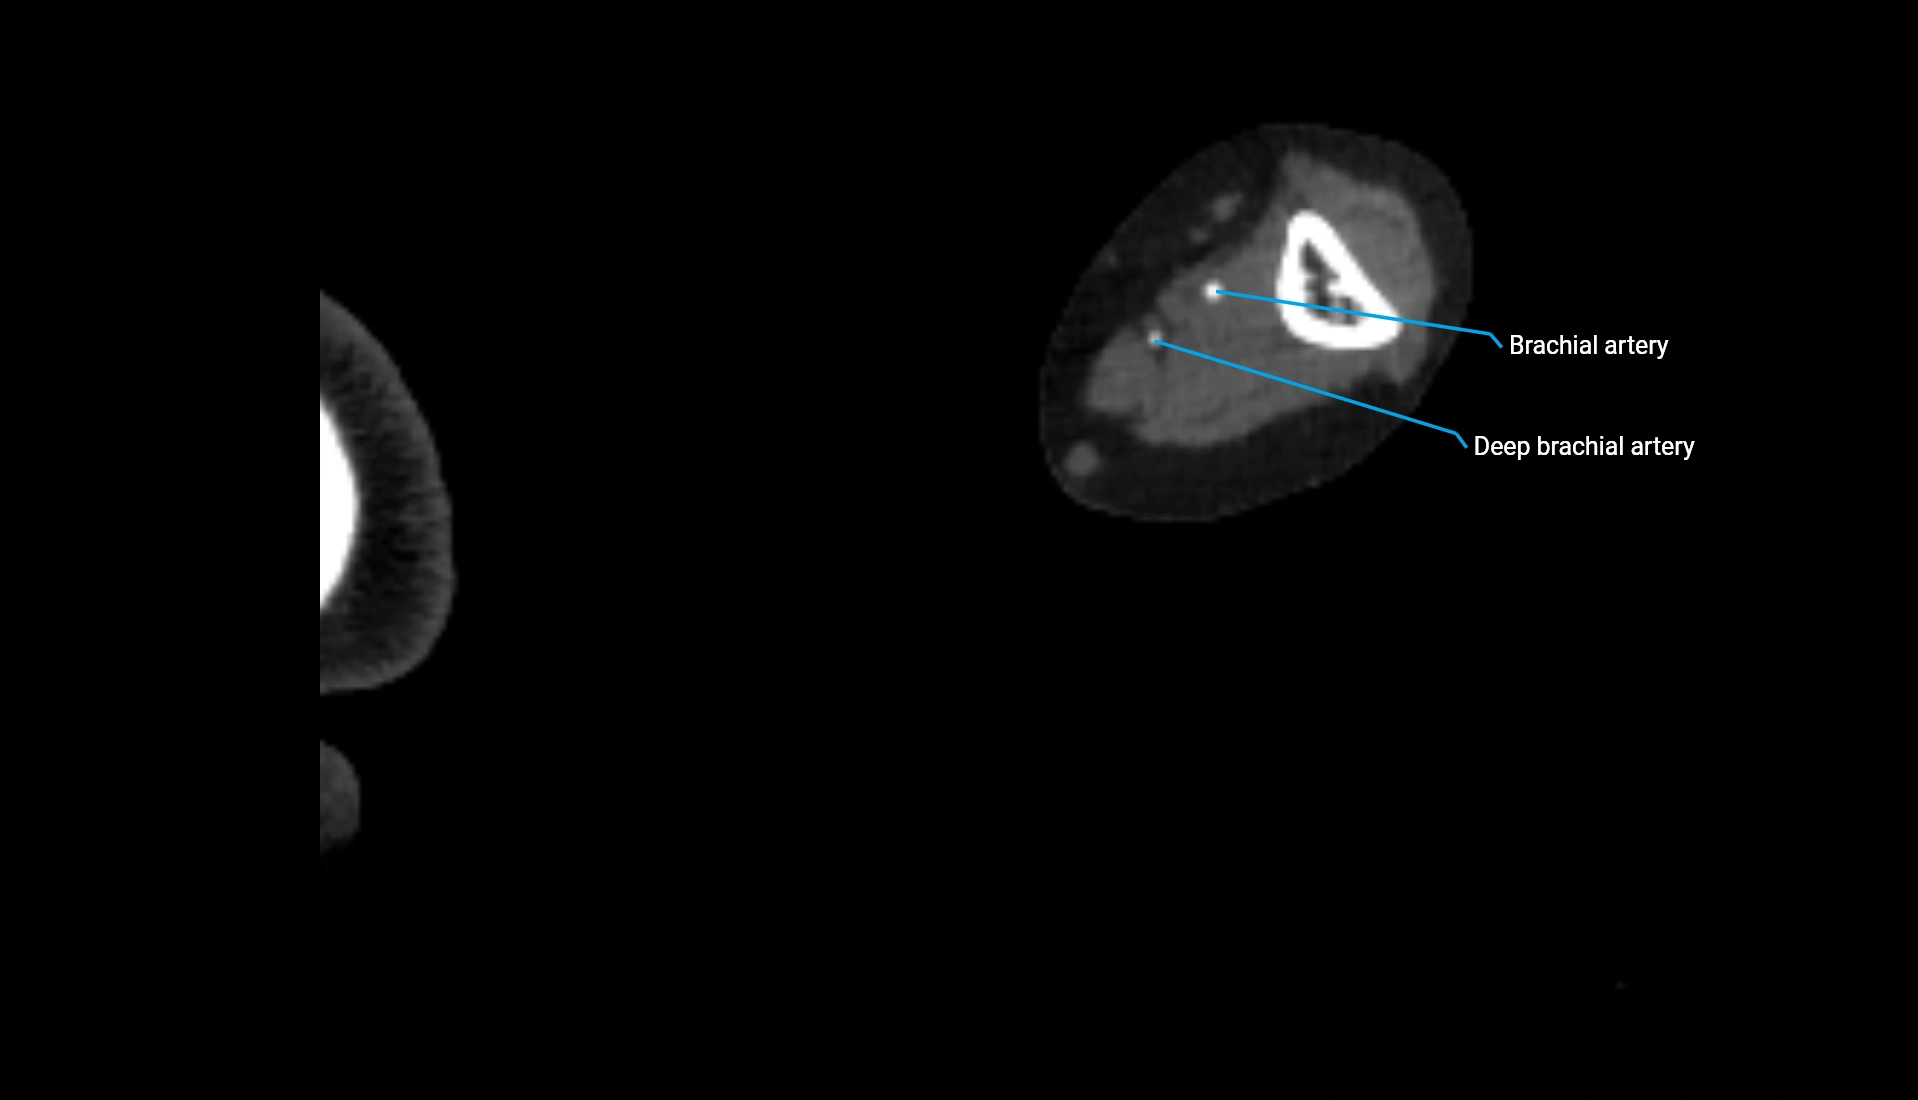

CT Appearance

Non-Contrast CT:

• Cortex: High-density, sharply defined

• Subchondral bone: Dense cancellous matrix

• Articular surface: Smooth concave contour articulating with the capitellum

• Excellent for evaluating bone integrity, alignment, and subtle fractures